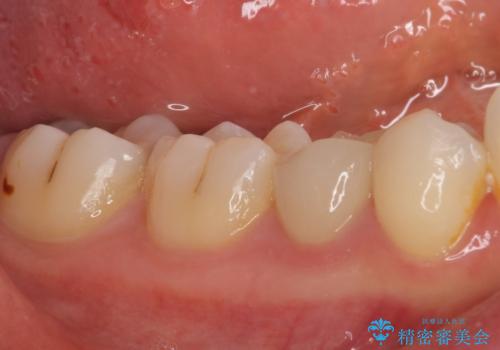

- 神経を抜く処置の後に装着したプラスチックのクラウンが外れてしまったとのことで来院された患者様です。

患者様自身、神経の取り除かれた歯はしっかりと製作されたクラウンを装着するべきと理解していただいていたため、オールセラミッククラウンにて補綴治療することとしました。

丈夫なクラウンを装着できただけでなく、形態や色調も自然に仕上げることができました。